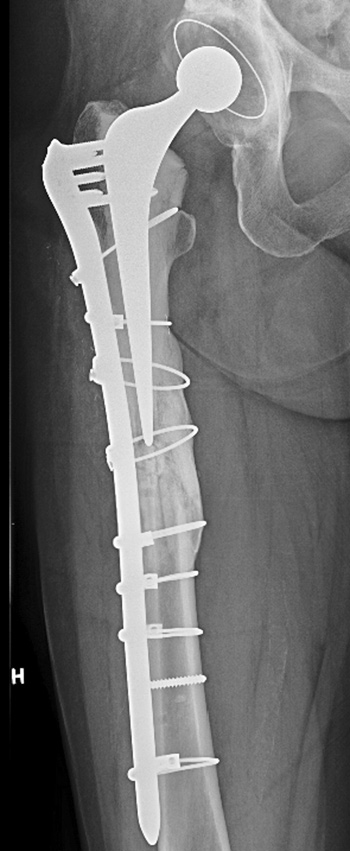

Det er bred enighet om at periprotetiske femurfrakturer etter hofteartroplastikk helst behandles med intern fiksasjon (3). Det svenske hofteregisteret rapporterer 34 % svikt av osteosyntesene ved denne frakturtypen. Når frakturene dessuten er atypiske, vil komplikasjonsraten kunne tenkes å bli enda høyere. Atypisk femurfraktur som oppstår periprotetisk, er ikke omtalt tidligere, så vidt vi kan se. Det gir ytterligere økt usikkerhet rundt prognosevurdering og behandlingsvalg.

Spesielt designede plater som gir en dynamisk kompresjon og som tillater at skruene settes vinkelstabilt og med ulik vinkel på platen, sikrer stabiliteten i konstruksjonen, samtidig som implantatet ikke kommer i konflikt med protesekomponenter eller sementmantel. Alternativt kan kabelcerclage erstatte en eller flere skruer. I løpet av det siste tiåret er det også utviklet platesystem som gjør det mulig å koble små endeplater til hovedplaten, proksimalt og/eller distalt, for å dekke hele femurs lengde. Adekvat fiksasjon av frakturen kan oppnås med bruk av disse implantatene, kombinert med strukturelle, kortikale transplantat formet som plater, og dessuten bruk av spongiøse beintransplantat (chips).

Denne behandlingsstrategien ble først implementert i sin helhet ved de kirurgiske revisjonene hos vår pasient og førte til at frakturene omsider helet.

Frakturlinjen ved atypiske frakturer er oftest helt horisontal eller viser en vinkling på maksimalt 30 grader (2). Figur 1 i artikkelen viser imidlertid en frakturlinje som har en vinkel som er over 30 grader, slik at jeg ikke mener den kan klassifiseres som atypisk. Jeg mangler også i den forbindelse opplysninger om skjelettstatus hos denne pasienten med multiple brudd. Hadde den langvarige bisfosfonatbehandling hatt effekt eller var pasienten fortsatt osteoporotisk? Hvis sistnevnte var tilfellet, burde man ha overveiet osteoanabol terapi med PTH, som pasienten kunne få på blå resept.